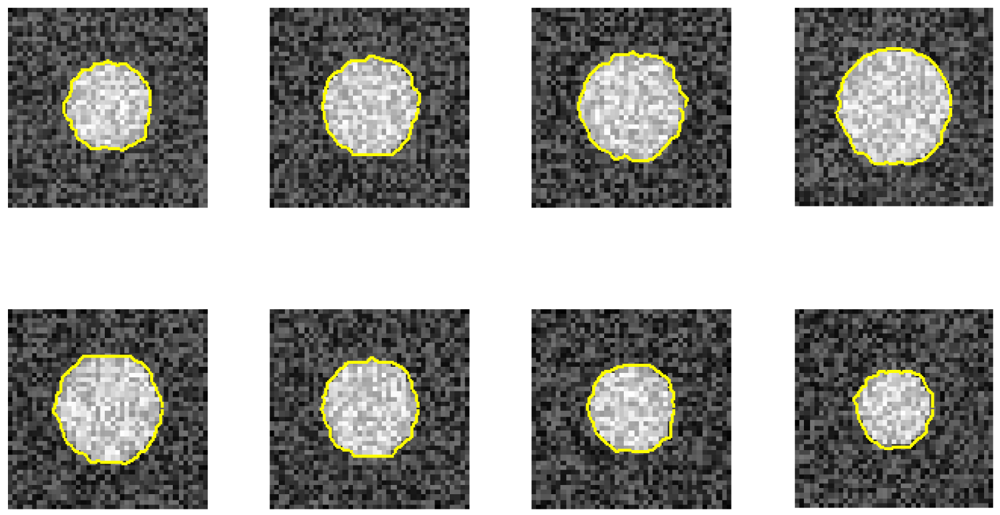

Figure 4 illustrates phantom images with different noise levels (SNR). To investigate the effects that these two parameters (resize factor and weighting factor s) have on accuracy, four different phantom image sequences, with SNR = 14, 16, 18, and 20 dB, are tested. Figure 5 shows the corresponding averaged accuracies. The z-axis in Figure 5 denotes the averaged unsigned error percentage (for eight images and ten experimental repetitions). The value of s is discretized from 0.01 to 0.21 with a step of 0.01. The resize factor value is discretized from 1 to 3 with a step of 0.1. From the results, we found that parameter s does not affect accuracy too much but the image-resize factor does impact accuracy. The optimal image resize factor value is 1.6, no matter the noise level. When SNR = 14 dB, the unsigned error ranges from 1.50% to 2.47% with resize factor = 1.6. The best accuracy appears when s = 0.01. Without image resize (factor = 1), the unsigned error ranges from 3.15% to 4.21%. The best accuracy appears when s = 0.02. When SNR = 20 dB, the unsigned error ranges from 0.77% to 1.62% with resize factor = 1.6. Without image resize (factor = 1), the unsigned error ranges from 3.05% to 3.46%. The best accuracy appears when s = 0.06. Figure 6 demonstrates the contour detection results (SNR = 14 dB).

Furthermore, we demonstrate the ability of the proposed method when one image is ruined. Figures 7 and 8 use the same eight phantom images (SNR = 14 dB), and their boundary detection results differ on the ruined image. The traditional DP has no knowledge about the third direction, and it fails to detect the boundary if the image is ruined. However, our method shows its robustness against strong noise.